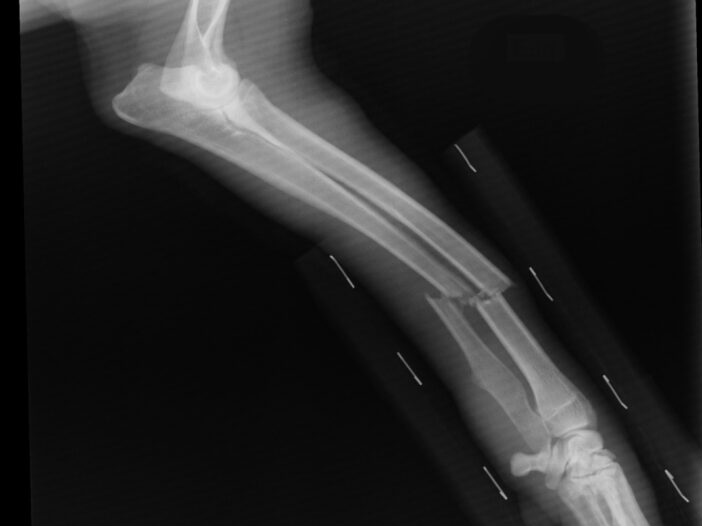

Nursing Home Errors: When Mistakes Become Broken Bones

When families entrust older people to nursing home care, they expect to encounter safe environments with proper supervision. Unfortunately, nursing home errors that lead to broken bones affect thousands of residents annually. Understanding how these preventable injuries may occur and what steps can be taken can make all the difference between suffering in silence and holding negligent facilities accountable.

Immediate Medical Response – Ensure your loved one receives proper medical attention. Even if staff claim the injury has been addressed, request evaluation by an independent physician or hospital emergency department. Many nursing home falls cause severe injuries requiring surgical procedures, and proper diagnosis prevents complications.

Secure Records and Contact Authorities – Request complete medical records, including X-rays, treatment notes, and follow-up recommendations. If you suspect criminal actions, contact law enforcement. Consider reporting to Adult Protective Services and your state’s Long-Term Care Ombudsman. Document all communications with nursing home staff.

Medical Evidence – Obtain complete medical records from the nursing home and treatment facilities, including diagnostic imaging, treatment plans, and complication documentation. Medical records provide a clear demonstration of injury severity and treatment adequacy.

Understanding Elderly Healing – Older adults heal more slowly than younger individuals, which can lead to additional complications. The healing process requires specialized attention as complications arise more easily, and recovery takes longer. Broken bones increase death risk for older people for up to 10 years, making proper care essential.

Advocating Treatment – Ensure your loved one receives appropriate medical care from qualified orthopedic specialists. Some breaks require surgery to align the bone fragments properly. Don’t hesitate to seek a second opinion if you are concerned about your treatment plan.